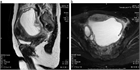

1. 下腹部痛・発熱・炎症反応上昇・膿瘍など画像所見・原因病原体の検出をもって診断する。